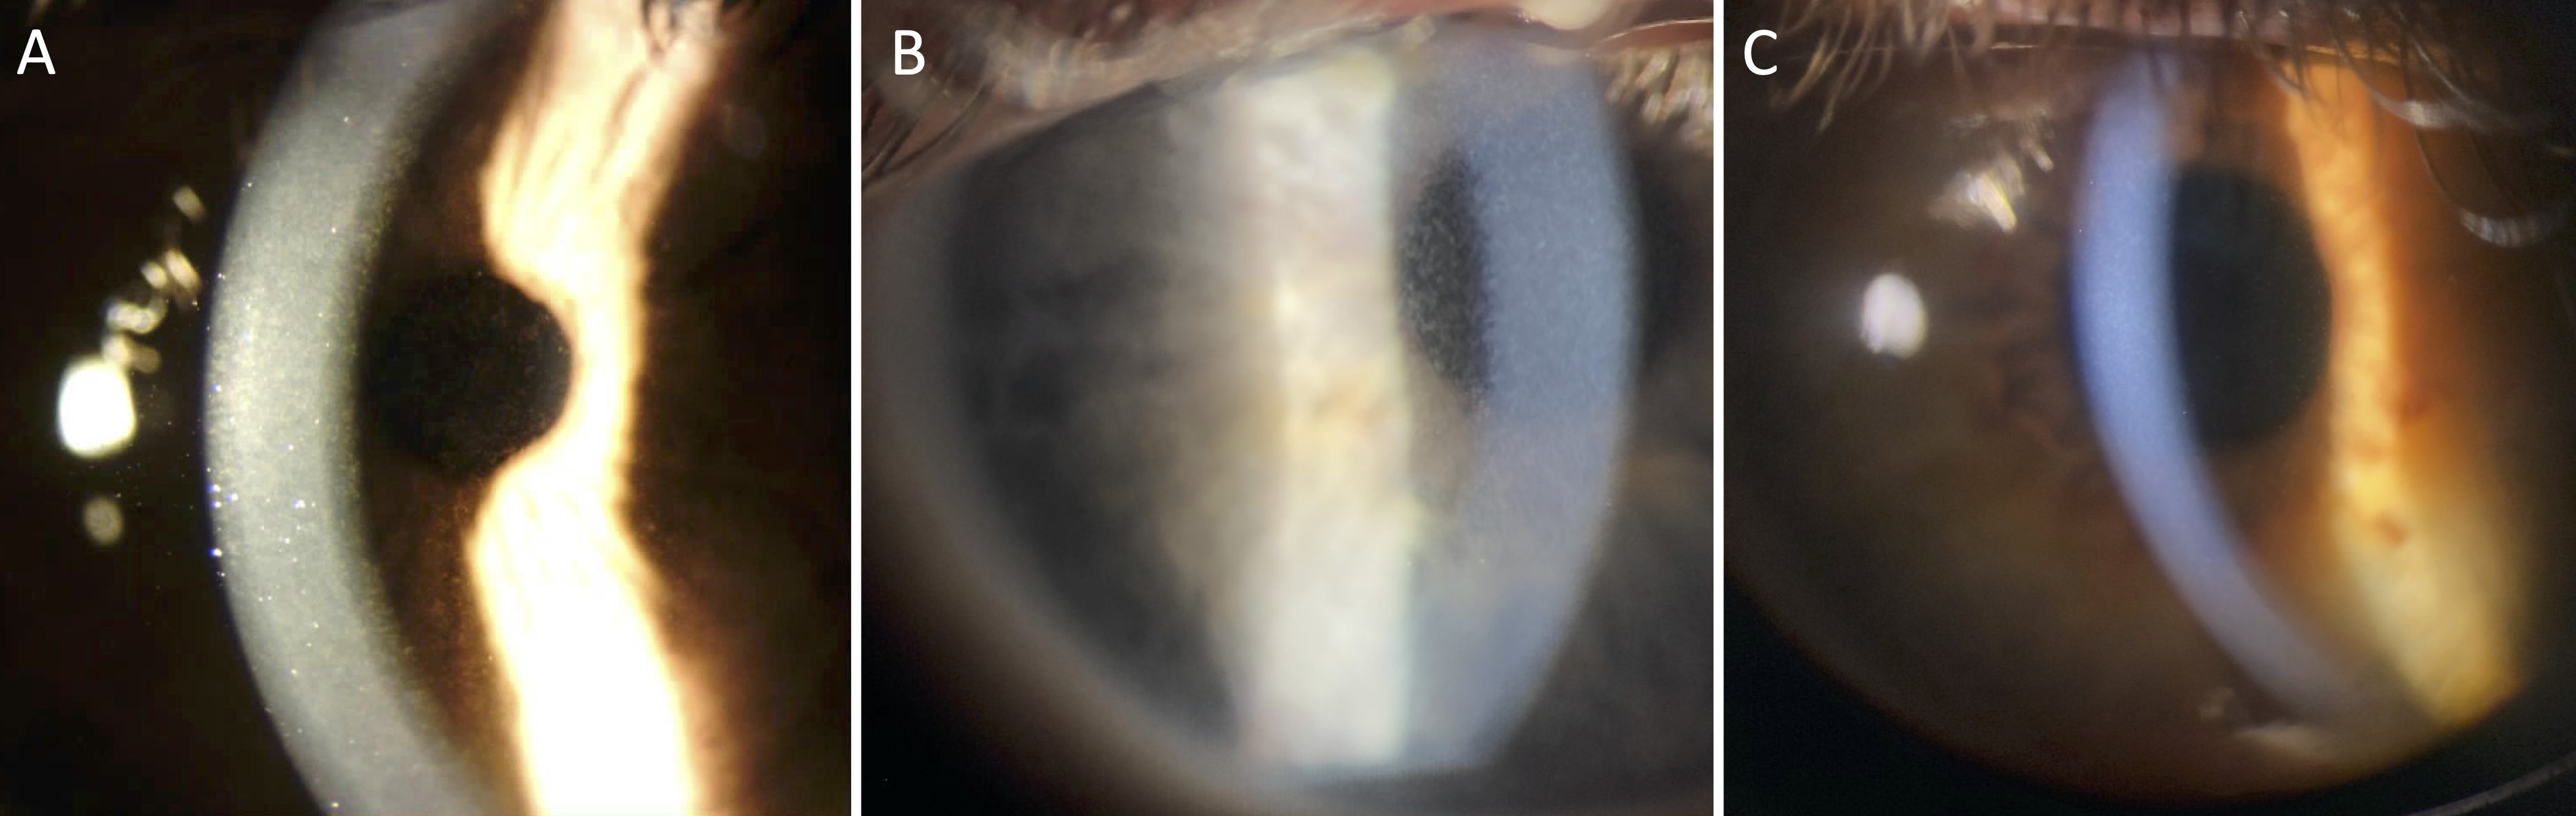

Figure 1. Slit-lamp photomicrographs of pre-Descemet corneal dystrophy. Slit-lamp examination of Case 1 (A, right eye), Case 2 (B, right eye), and Case 3 (C, left eye) demonstrating diffuse, punctate, white-gray opacities in the posterior stroma anterior to the Descemet membrane.